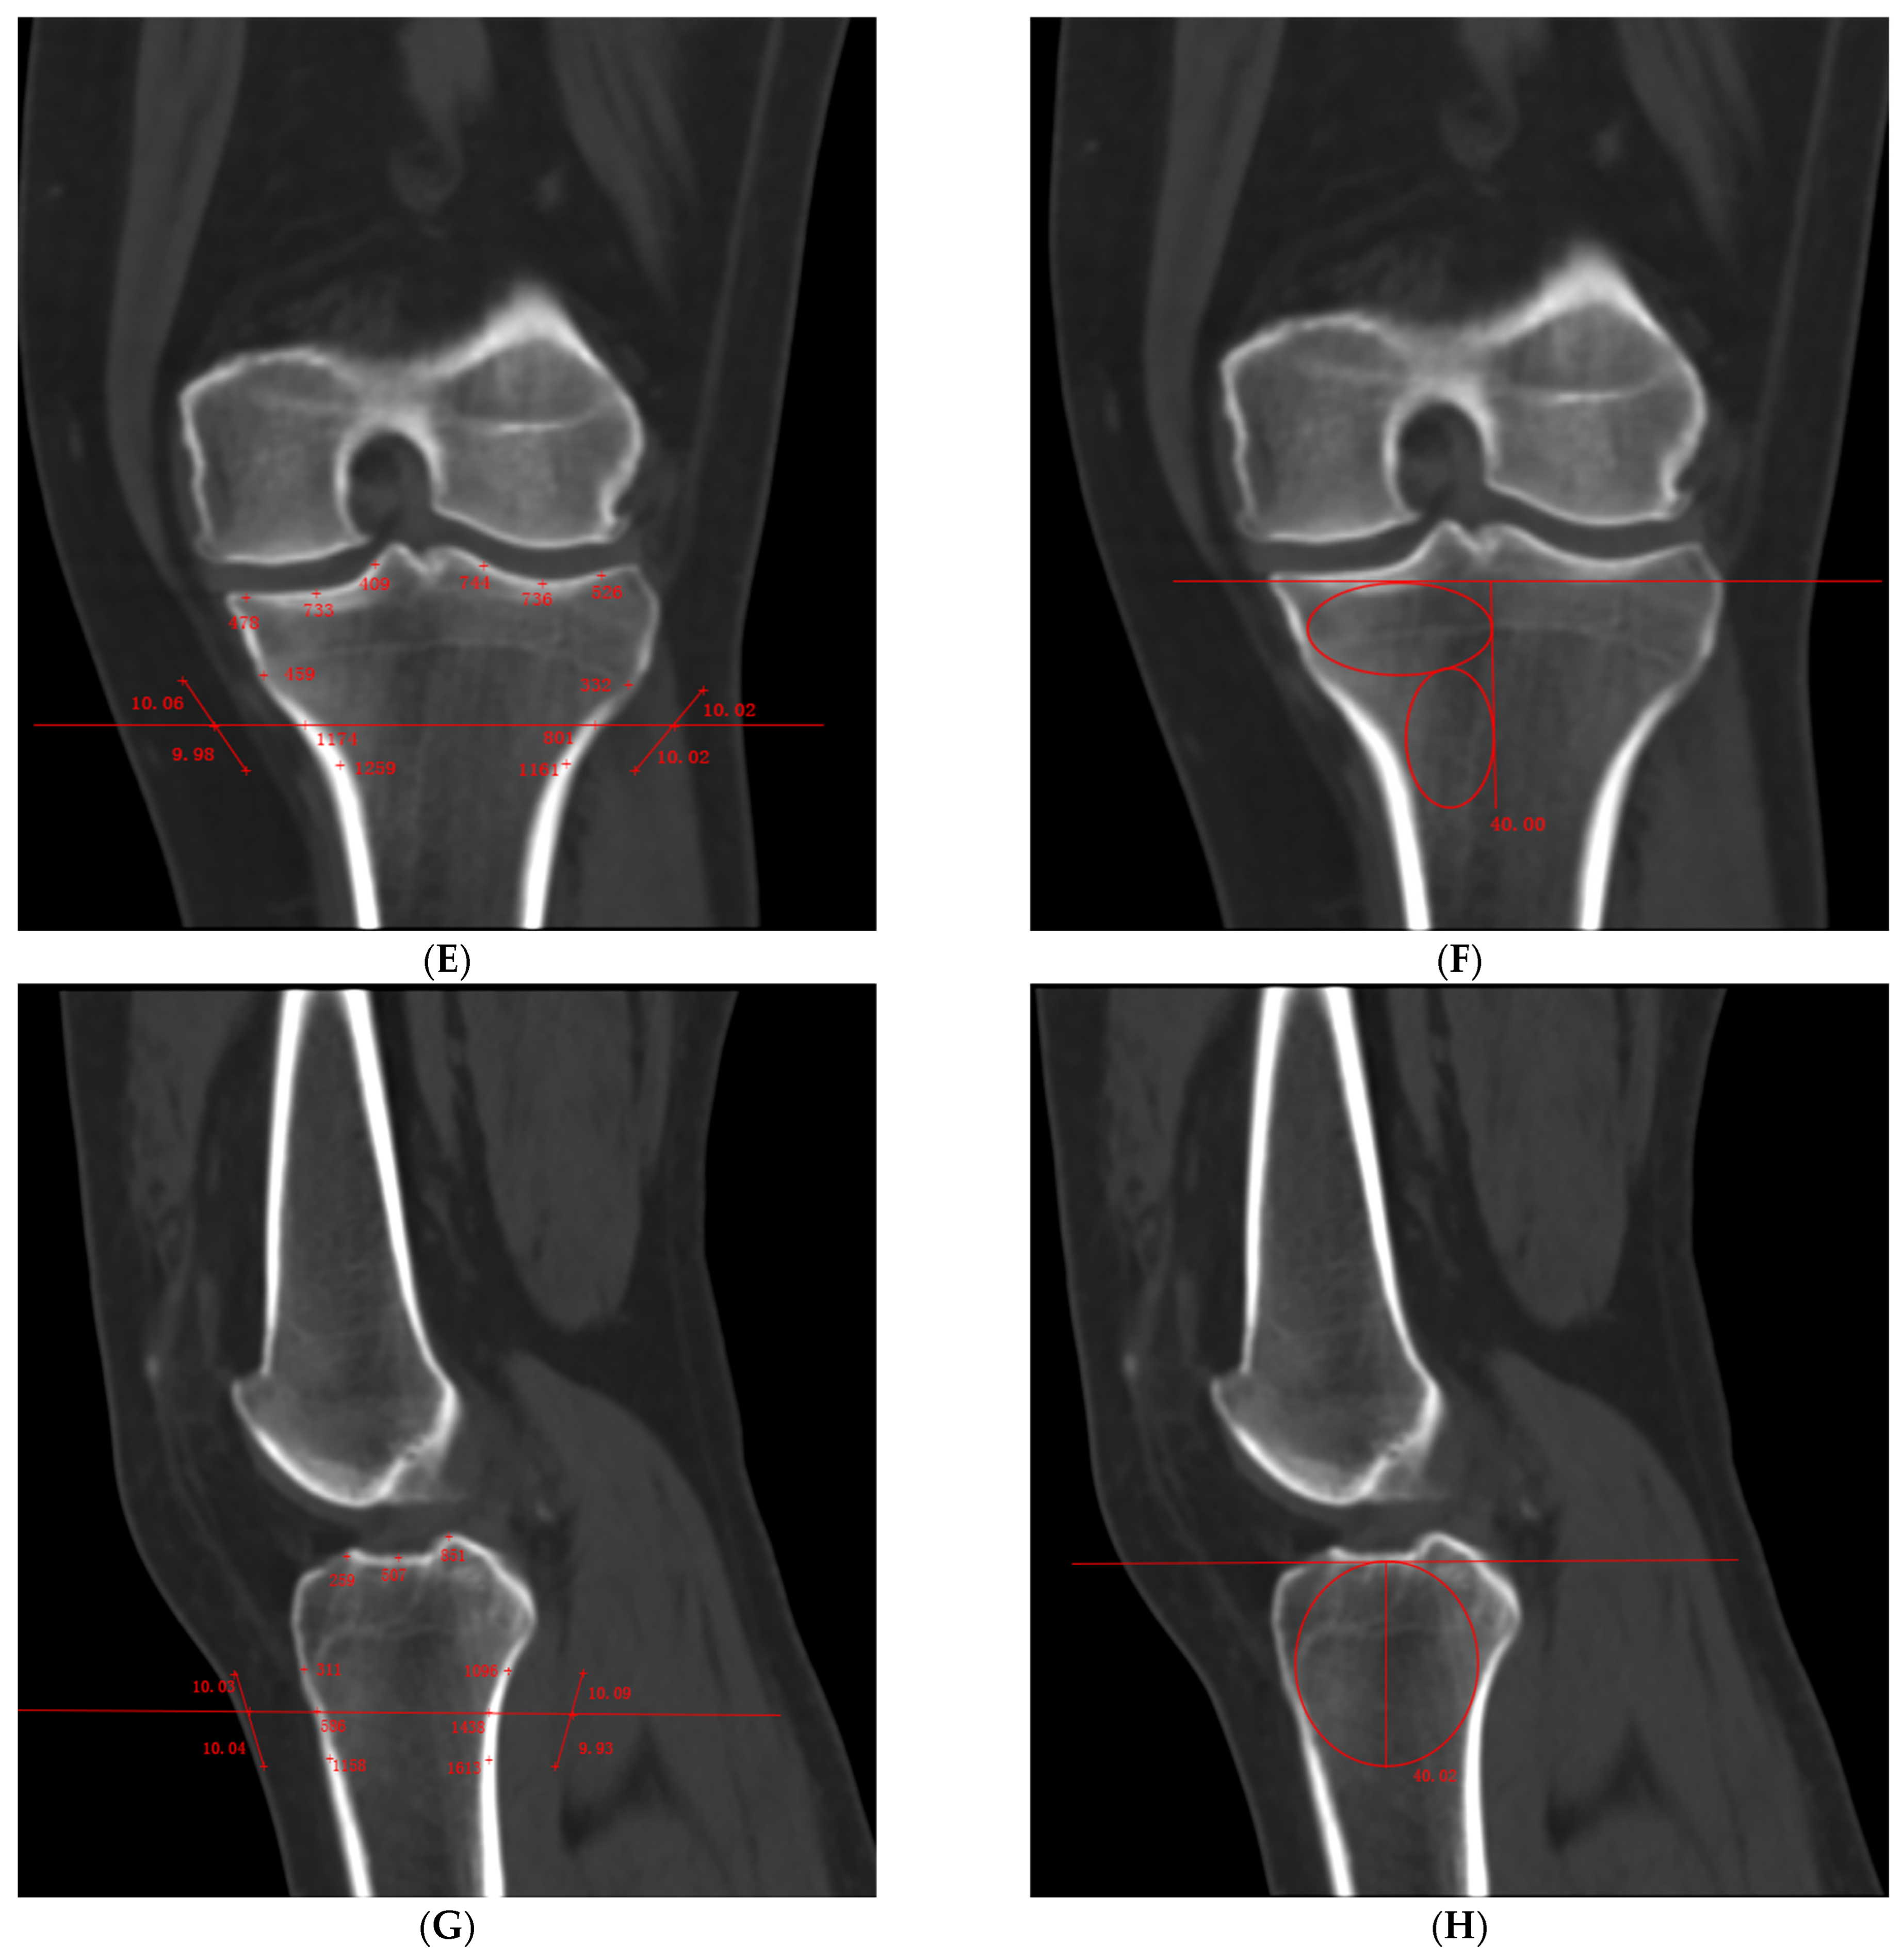

- Cortical Bone HU Value: We measured at the transitional area between the medial tibial condyle and the shaft (within ± 1 cm above and below this region), taking three points along the lateral tibial cortex parallel to the medial tibial surface as well as three evenly spaced points on both the medial and lateral tibial plateaus (Figure 2E).

- Medial Condyle Cancellous Bone HU Value: We drew a 4 cm vertical line downward from the lateral intercondylar eminence, avoiding the cortical bone, and measured within the fixed region (Figure 2F).

- Cortical Bone HU Value: We measured at the transitional area between the anterior tibial condyle and the shaft (within ± 1 cm above and below this region), taking three points along the posterior cortex of the tibia parallel to the anterior tibial surface as well as three evenly spaced points on the tibial plateau (Figure 2G).

- Medial Condyle Cancellous Bone HU Value: We drew a 4 cm vertical line downward from the tibial plateau, avoiding the cortical bone, and measured within the fixed region (Figure 2H).